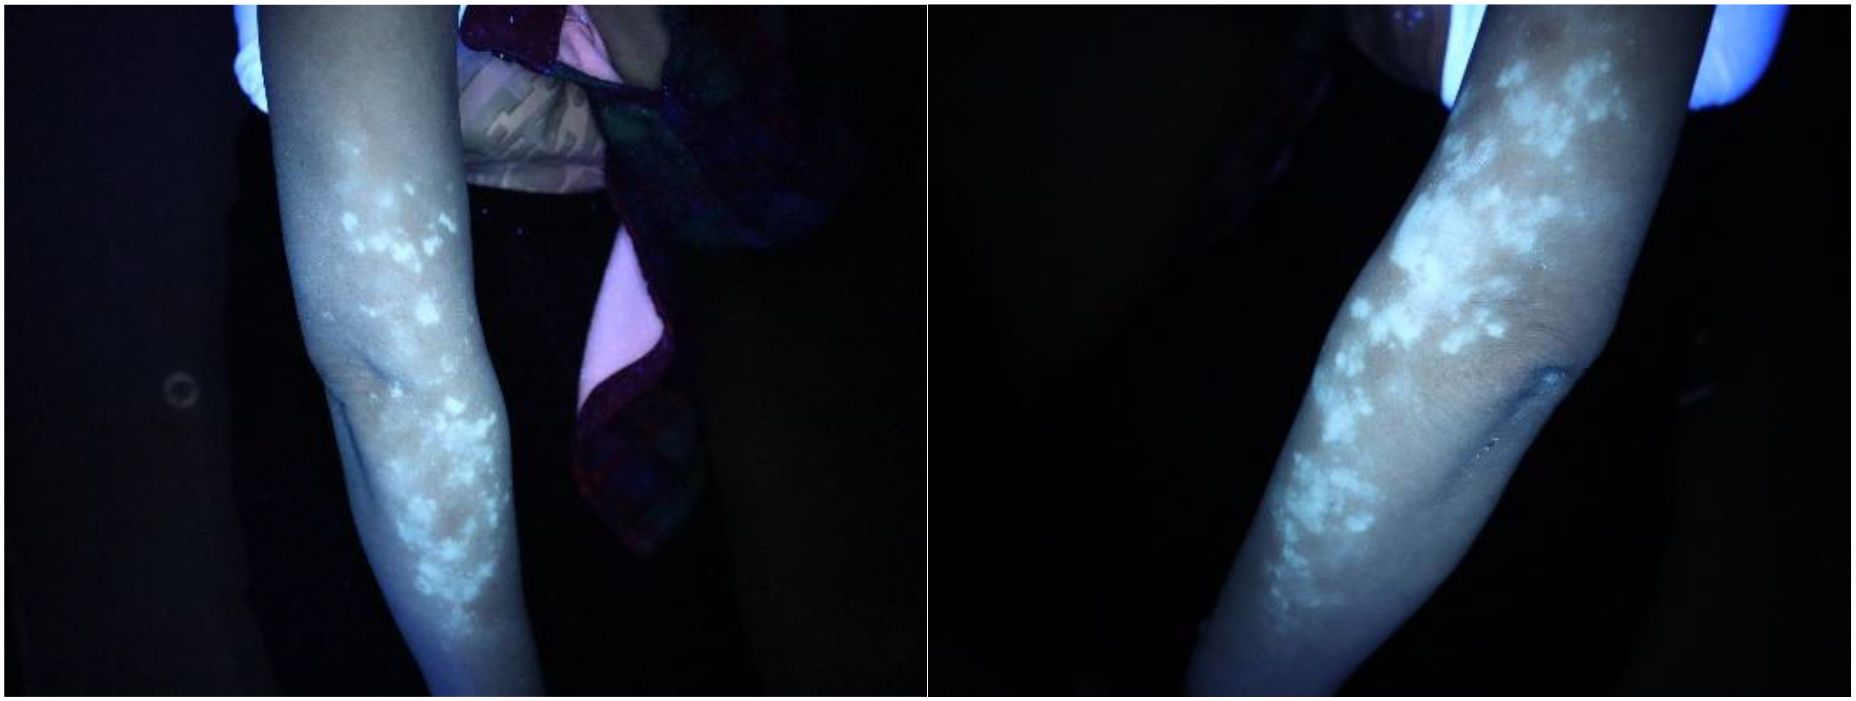

Sixteen months after the start of treatment, pruritus appeared on the forearm, accompanied by depigmented spots. The patient herself and her family had no previous history of autoimmune diseases. Dermoscopy showed: pigment disappearance in the lesion area, deepened pigment around the lesion, and telangiectasia, suggesting vitiligo (see Figure 1). Immunofluorescence and Wood’s lamp examination showed bright blue-white fluorescence(see Figure 2). She was treated with 0.1% mometasone cream and 0.1% tacrolimus ointment. The follow-up after 2 months showed stable condition, and no new lesions appeared in other parts.

Two images showing a forearm under UV light, revealing white patches consistent with vitiligo. The left image highlights the right outer arm, while the right image focuses on the left outer arm, both showing a similar pattern of depigmentation.

Figure 2. Under Wood’s lamp, the lesion area showed bright blue-white fluorescence, which was in significant contrast with the surrounding normal skin, consistent with the characteristic manifestations of vitiligo.